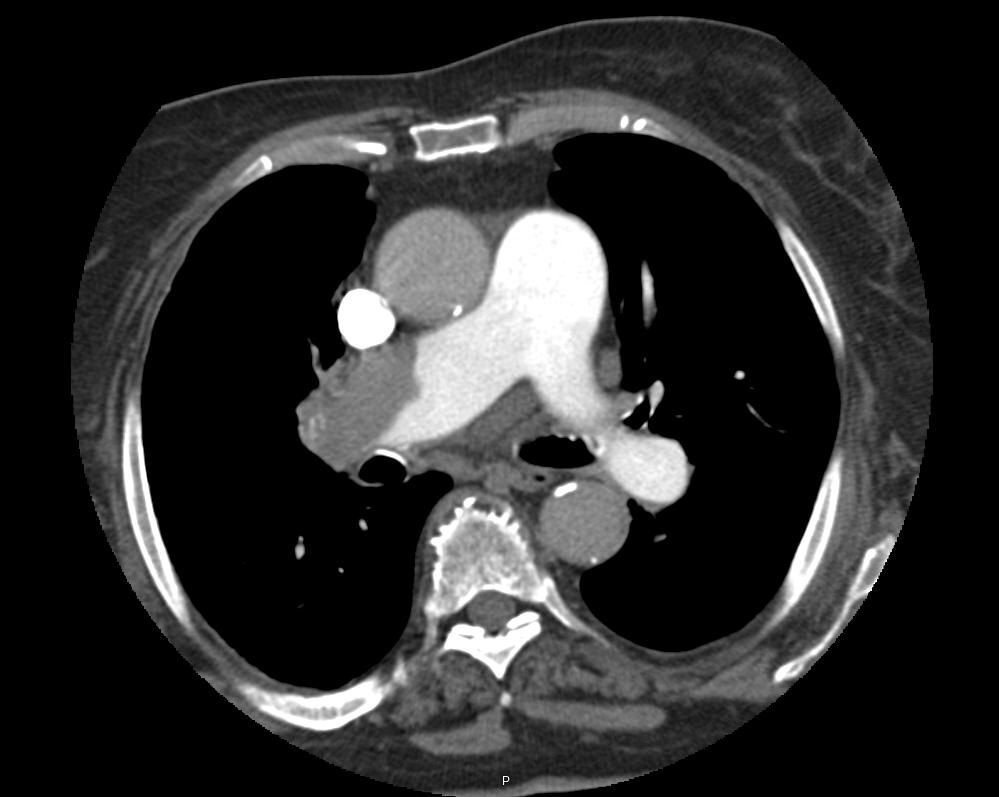

Повышенный Д-димер не говорит ни о чем (анализ, получивший популярность в народе после пандемии COVID-19). А вот нормальный - о том, что в настоящий момент в организме тромбы не образуются. Что не означает, что они не захотят образоваться завтра (или сегодня к вечеру). Поэтому любая ТЭЛА должна быть подтверждена визуализацией. Золотой стандарт - внутривенное болюсное контрастирование легочной артерии (КТ-ангиография). Без этого любое подозрение на ТЭЛА является лишь подозрением (исключение - ургентные случаи, когда больной не в состоянии доехать до обследования, но это отдельная долгая история).